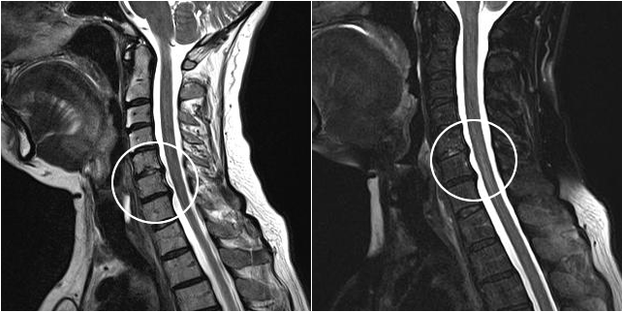

Os métodos diagnósticos modernos incluem ressonância magnética e tomografia computadorizada, que permitem examinar com mais precisão os processos de destruição da cartilagem e do tecido ósseo. Além disso, usando esta técnica é conveniente diagnosticar hérnias e outros defeitos de tecidos moles próximos à origem da doença.